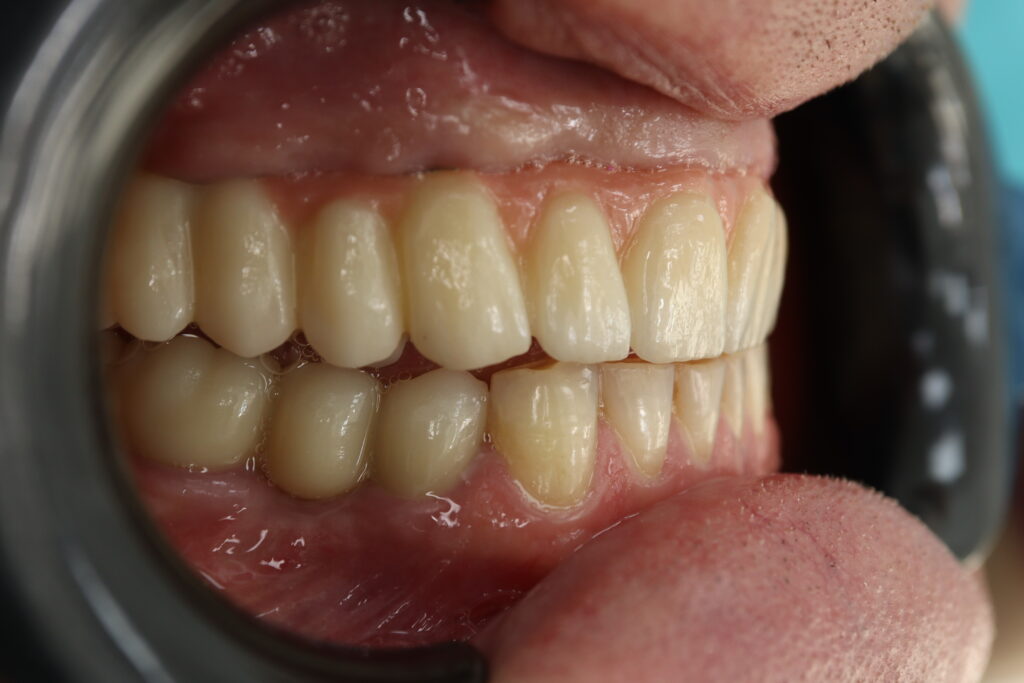

Результат

Пациенту были установлены 6 имплантатов Megagen AnyOne по системе All-on-6 на верхней челюсти и 4 имплантата на нижней по классической двухэтапной методике.

Спустя 27 дней был зафиксирован протез с опопрой на дентальные имплантаты из диоксида циркония с каркасом из титана.

Также на нижнюю челюсть был изготовлен мостовидный протез из 4х коронок (цирконий) с опорой на 3 индивидуальных абатмента с одной стороны и 1 коронка на иплантат с другой.